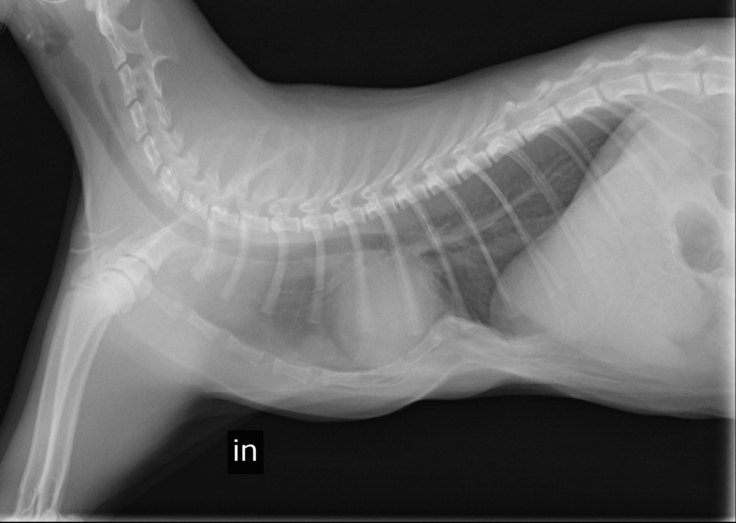

現状報告②検診結果をご報告します

本日術後の検診に行ってきました。

胸骨は正常な位置に留まっており、

経過は良好なようです。

今回の検診で撮影したレントゲン写真と診療明細書の写真を添付しておきます。

☟息を吸っている所です